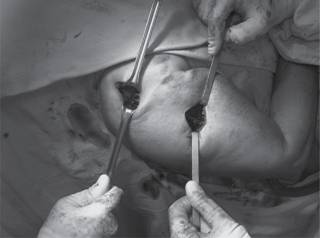

Bajo anestesia general, el paciente en decúbito supino en posición de silla de playa se inicia abordaje lateral acromial sin sobrepasar 5 cm de la punta del acromion, se diseca entre el deltoides anterior y medio, se hace disección y exposición de la cabeza humeral. Posteriormente se realiza fijación de manera percutánea con un clavo de Kirschner y se procede, bajo revisión fluoroscópica, a visualizar reducción de fractura de la metáfisis y tuberosidades (Figura 1). Se coloca placa sobre la piel ejerciendo una presión de impronta para determinar longitud y se realiza incisión distal (Figura 2). Teniendo en cuenta previa palpación y disección del nervio axilar, se desliza la placa (Figura 3) y se fija proximalmente con 3 tornillos autobloqueados en la cabeza (los tornillos más distales del implante en la posición A y B ), en algunas ocasiones se usan los tornillos de la posición C y se revisa bajo fluoroscopio reducción y posición de los tornillos y posteriormente con tornillo de cortical se adosa placa al hueso para luego colocar tornillos corticales o de bloqueo diafisarios y el tornillo de bloqueo distal (Figura 4).